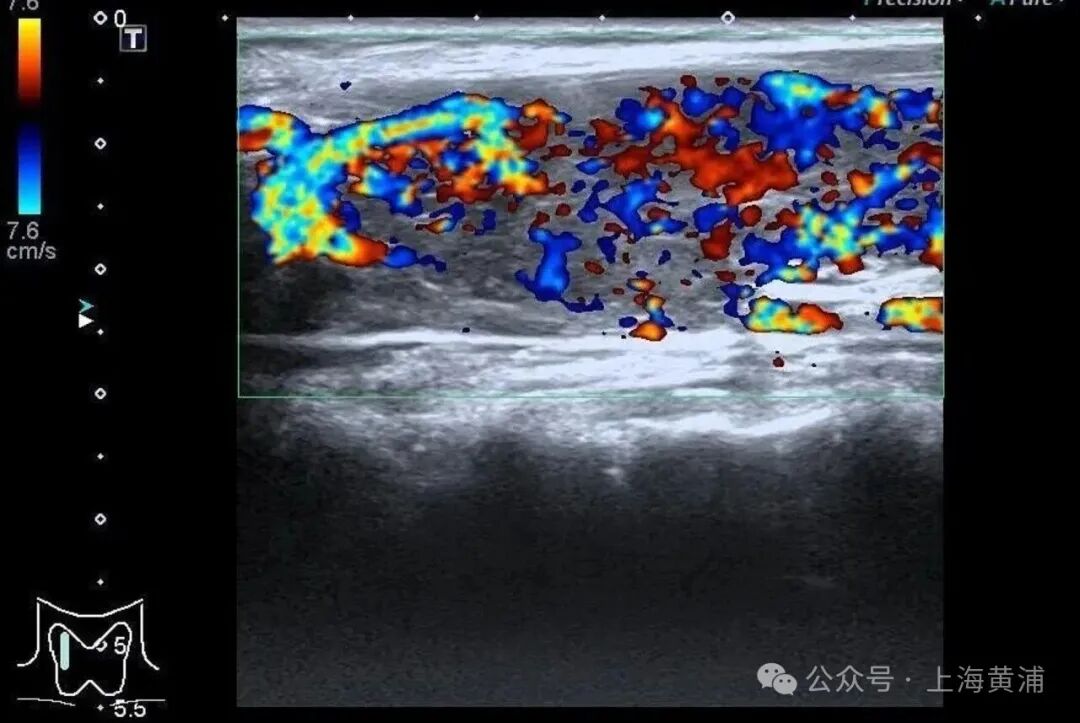

入院后的检查结果显示

陈女士的身体

正被一场“激素风暴”席卷

甲状腺功能检查中,游离T3高达20.83pmol/L(正常值3.5-6.5pmol/L),游离T4高达88.42pmol/L(正常值11.5-22.7pmol/L),这两项核心激素都超过正常上限数倍,而本应调控它们的促甲状腺激素(TSH)却几乎测不出来,这明确证实了陈女士患有极其严重的甲状腺毒症。心脏超声结果同样不容乐观,射血分数仅有40%(正常应高于55%),这意味着心脏泵血能力大幅下降。

同时,CT检查发现她的双侧胸腔、腹腔存在积液。综合各项检查结果,医生判断陈女士患上了甲状腺危象,这是甲亢最凶险的并发症。